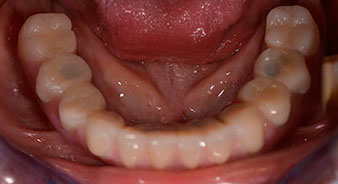

The impression and bite registration were then performed so that the dental technician could begin producing the provisional restoration immediately. This was then screwed in on the same day (Fig. 17 and 18).

Implants

Fig. 17

Fig. 18

Following the time required for the osseointegration, the final impression of the implants could be performed and the final denture produced accordingly (Fig. 19 and 20). At this point, the dentist and patient were able to decide together whether to use a ceramic or acrylic veneer and a zirconium or metal framework. In this case, Dr. Pascu’s team decided on an acrylic veneer based on the unclear prognosis for the maxillary dentition and the fact that tooth 24 is elongated. This type of veneer is generally considerably easier to adapt and can thus be subsequently altered to reflect the new situation in the maxilla.